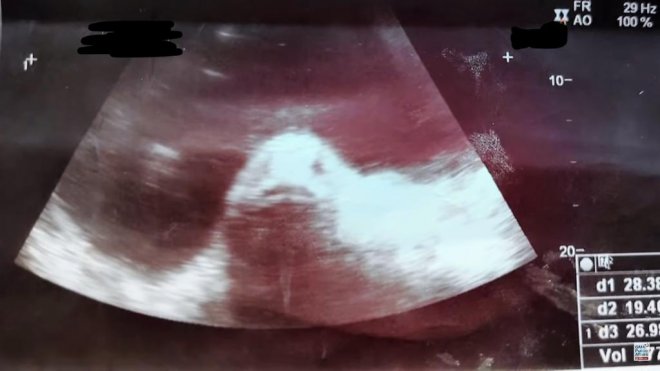

這起被形容為「海中異性入侵少女體內致懷孕」的驚悚事件,發生於2017年6月份,卻於近日才在網絡上瘋傳,吸引不少國外媒體報導。而該少女超音波掃瞄照片也爆光,腹中竟然出現了「魚臉」!

家人以為她生活不檢點,在外面與男人胡亂搞關係,結果懷孕了,馬上就帶她上醫院檢查。醫生為貝茜娜進行了超音波掃瞄,螢幕上出現的竟然是「一條魚」,而且還露出了可愛的魚臉!

她再次回到醫院進行檢查,檢查報告竟然是卵巢囊腫,根本不是什麼魚寶寶!原來是巢囊腫,才讓她的體重一下子從40公斤飆升到50公斤,而且也會感覺疼痛。